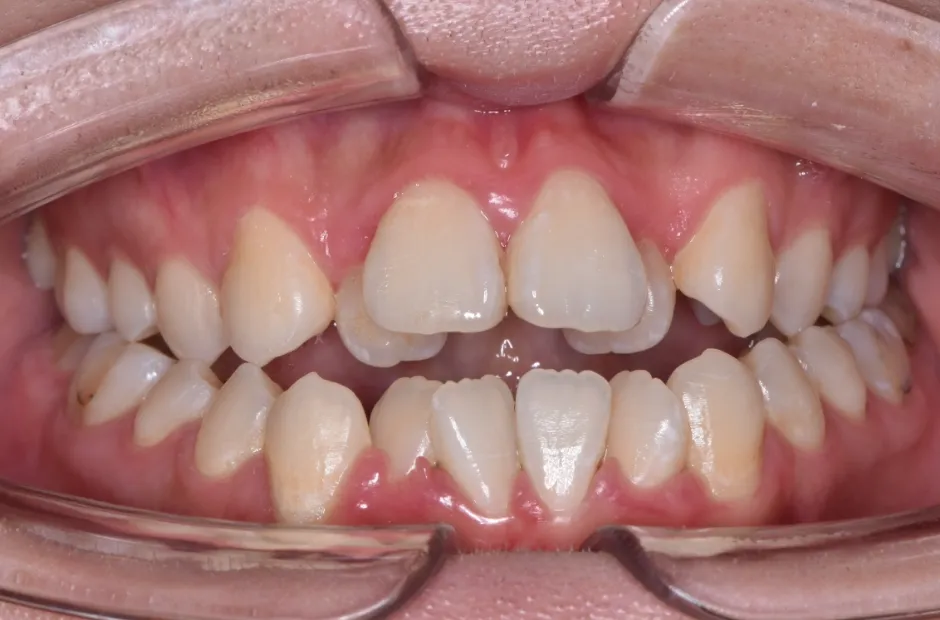

叢生

| 診断名・主訴 | 叢生 |

|---|---|

| 年齢・性別 | 43歳・女性 |

| 治療期間・回数 | 2年7か月 27回 |

| 治療に用いた主な装置 | 舌側矯正 |

| 抜歯部位 | 両顎4,4 |

| 治療費 | 100万円(税抜) |

| リスク・副作用 | 装置による違和感・疼痛・歯肉退縮・歯根吸収・虫歯のリスクなど |

治療前